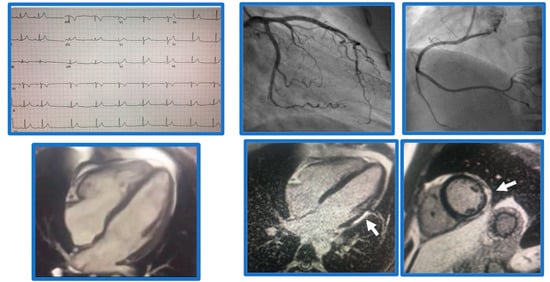

5. Myocarditis

6. Acute MI